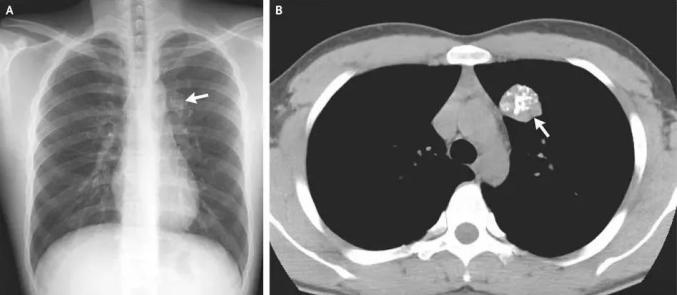

事实上,在X线片, CT、钼靶和超声波报告中经常出现“钙化”和“钙化炉”这两个词。根据《生命时报》,钙化是指体内钙离子以磷酸盐或碳酸盐的形式沉积的过程。很多钙化是在身体病变修复过程中形成的,整个过程类似于伤口修复结痂。通常表现为钙和盐沉积在受损组织中,使这些组织变得坚硬。

钙化可能发生在身体的大部分组织和器官中,如头部的脑膜、基底节区、胸部的肺、肋软骨、胸骨剑突、腹部的肝肾、甲状腺、乳腺、前列腺等腺管,以及大多数遍布身体的动脉和静脉血管。钙化的广泛性也使其成为影像学报告中的“常客”,用于体检和正常检查。

航空总医院影像科副主任申太忠说:“钙化不是一种疾病,而是一种体征。”钙化是否会影响健康,取决于其部位、影像特征和患者临床症状。

通过检测钙化的位置和水平,医生可以及时发现和诊断疾病,了解疾病的进展,评估治疗效果。钙化的发生与各种因素有关。

疾病:一些慢性疾病可能会诱发钙化。比如糖尿病长期得不到有效控制,会导致高血糖和新陈代谢紊乱,影响肾脏对钙的排泄和新陈代谢,导致钙化。疾病的修复和治愈也会导致钙化。例如,结核性肺炎病变区的组织可能在炎症后的修复过程中形成钙化。